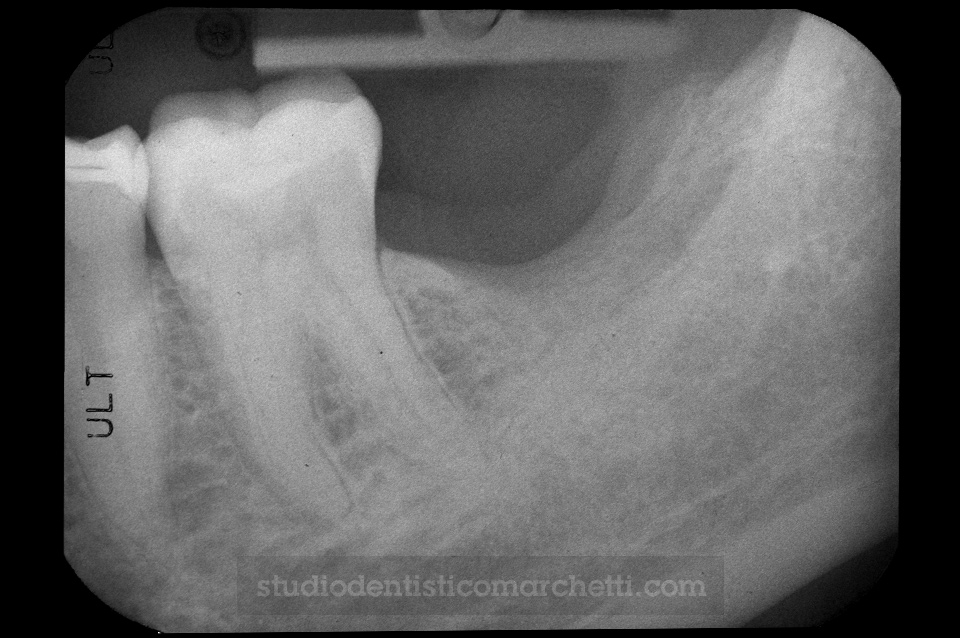

Chirurgia Orale

Estrazione di Dente del Giudizio Incluso

Chirurgia Orale

Estrazione di Dente del Giudizio Incluso

Chirurgia Orale

Estrazione di Dente del Giudizio Incluso